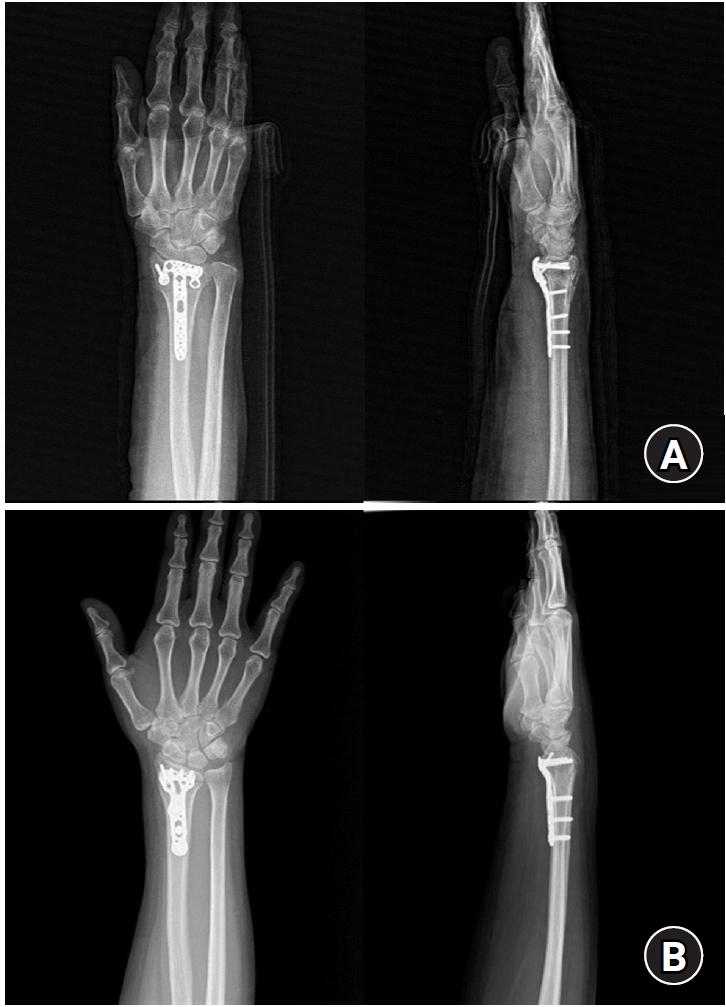

Fig. 4.

Postoperative radiographs (anteroposterior and lateral). (A) A 2.4 mm variable angle locking compression plate volar rim distal radius plate (Synthes) used for fixation in a distal radius fracture with a volar lunate facet fragment. (B) Acu-Loc volar distal radius plate (Acumed) used for fixation in a distal radius fracture with a volar lunate facet fragment.

jmt-2025-00241f4.jpg

Fig. 4. Postoperative radiographs (anteroposterior and lateral). (A) A 2.4 mm variable angle locking compression plate volar rim distal radius plate (Synthes) used for fixation in a distal radius fracture with a volar lunate facet fragment. (B) Acu-Loc volar distal radius plate (Acumed) used for fixation in a distal radius fracture with a volar lunate facet fragment.